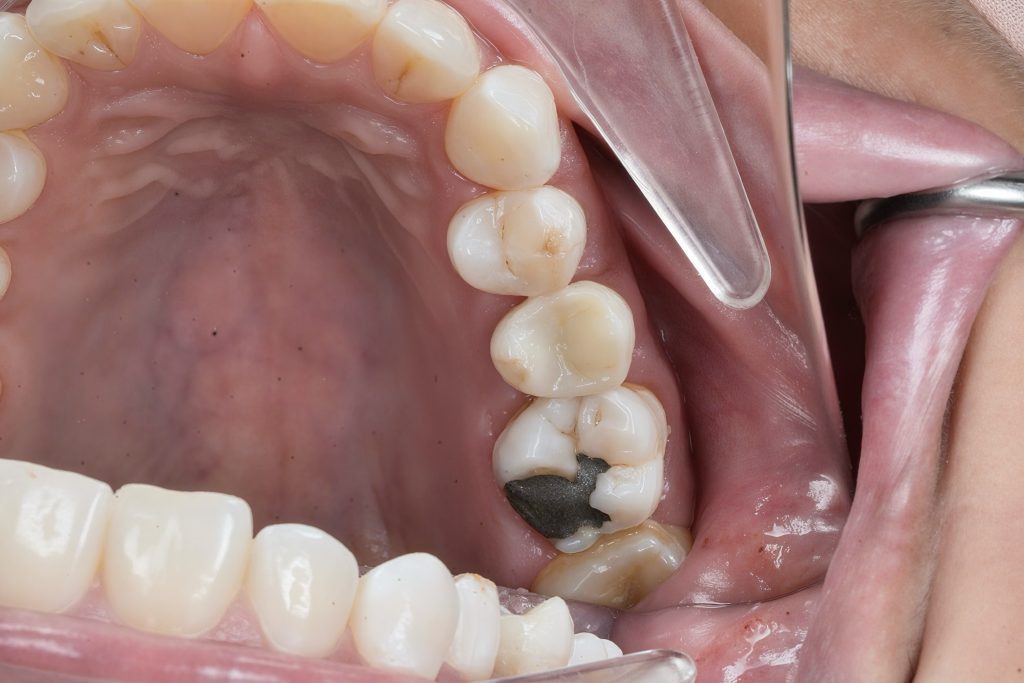

Patient reported food impaction and sensitivity during mastication between upper posterior teeth.

Clinical and radiographic exam confirmed adjacent Class II carious lesions affecting both teeth, with secondary caries beneath existing composite and defective margins.

Rubber dam isolation achieved using clamp stabilization to maintain a dry and clean operative field – essential for adhesive dentistry (Fig 1–2).

- Preoperative occlusal view showing defective composite & caries

- Rubber dam isolation